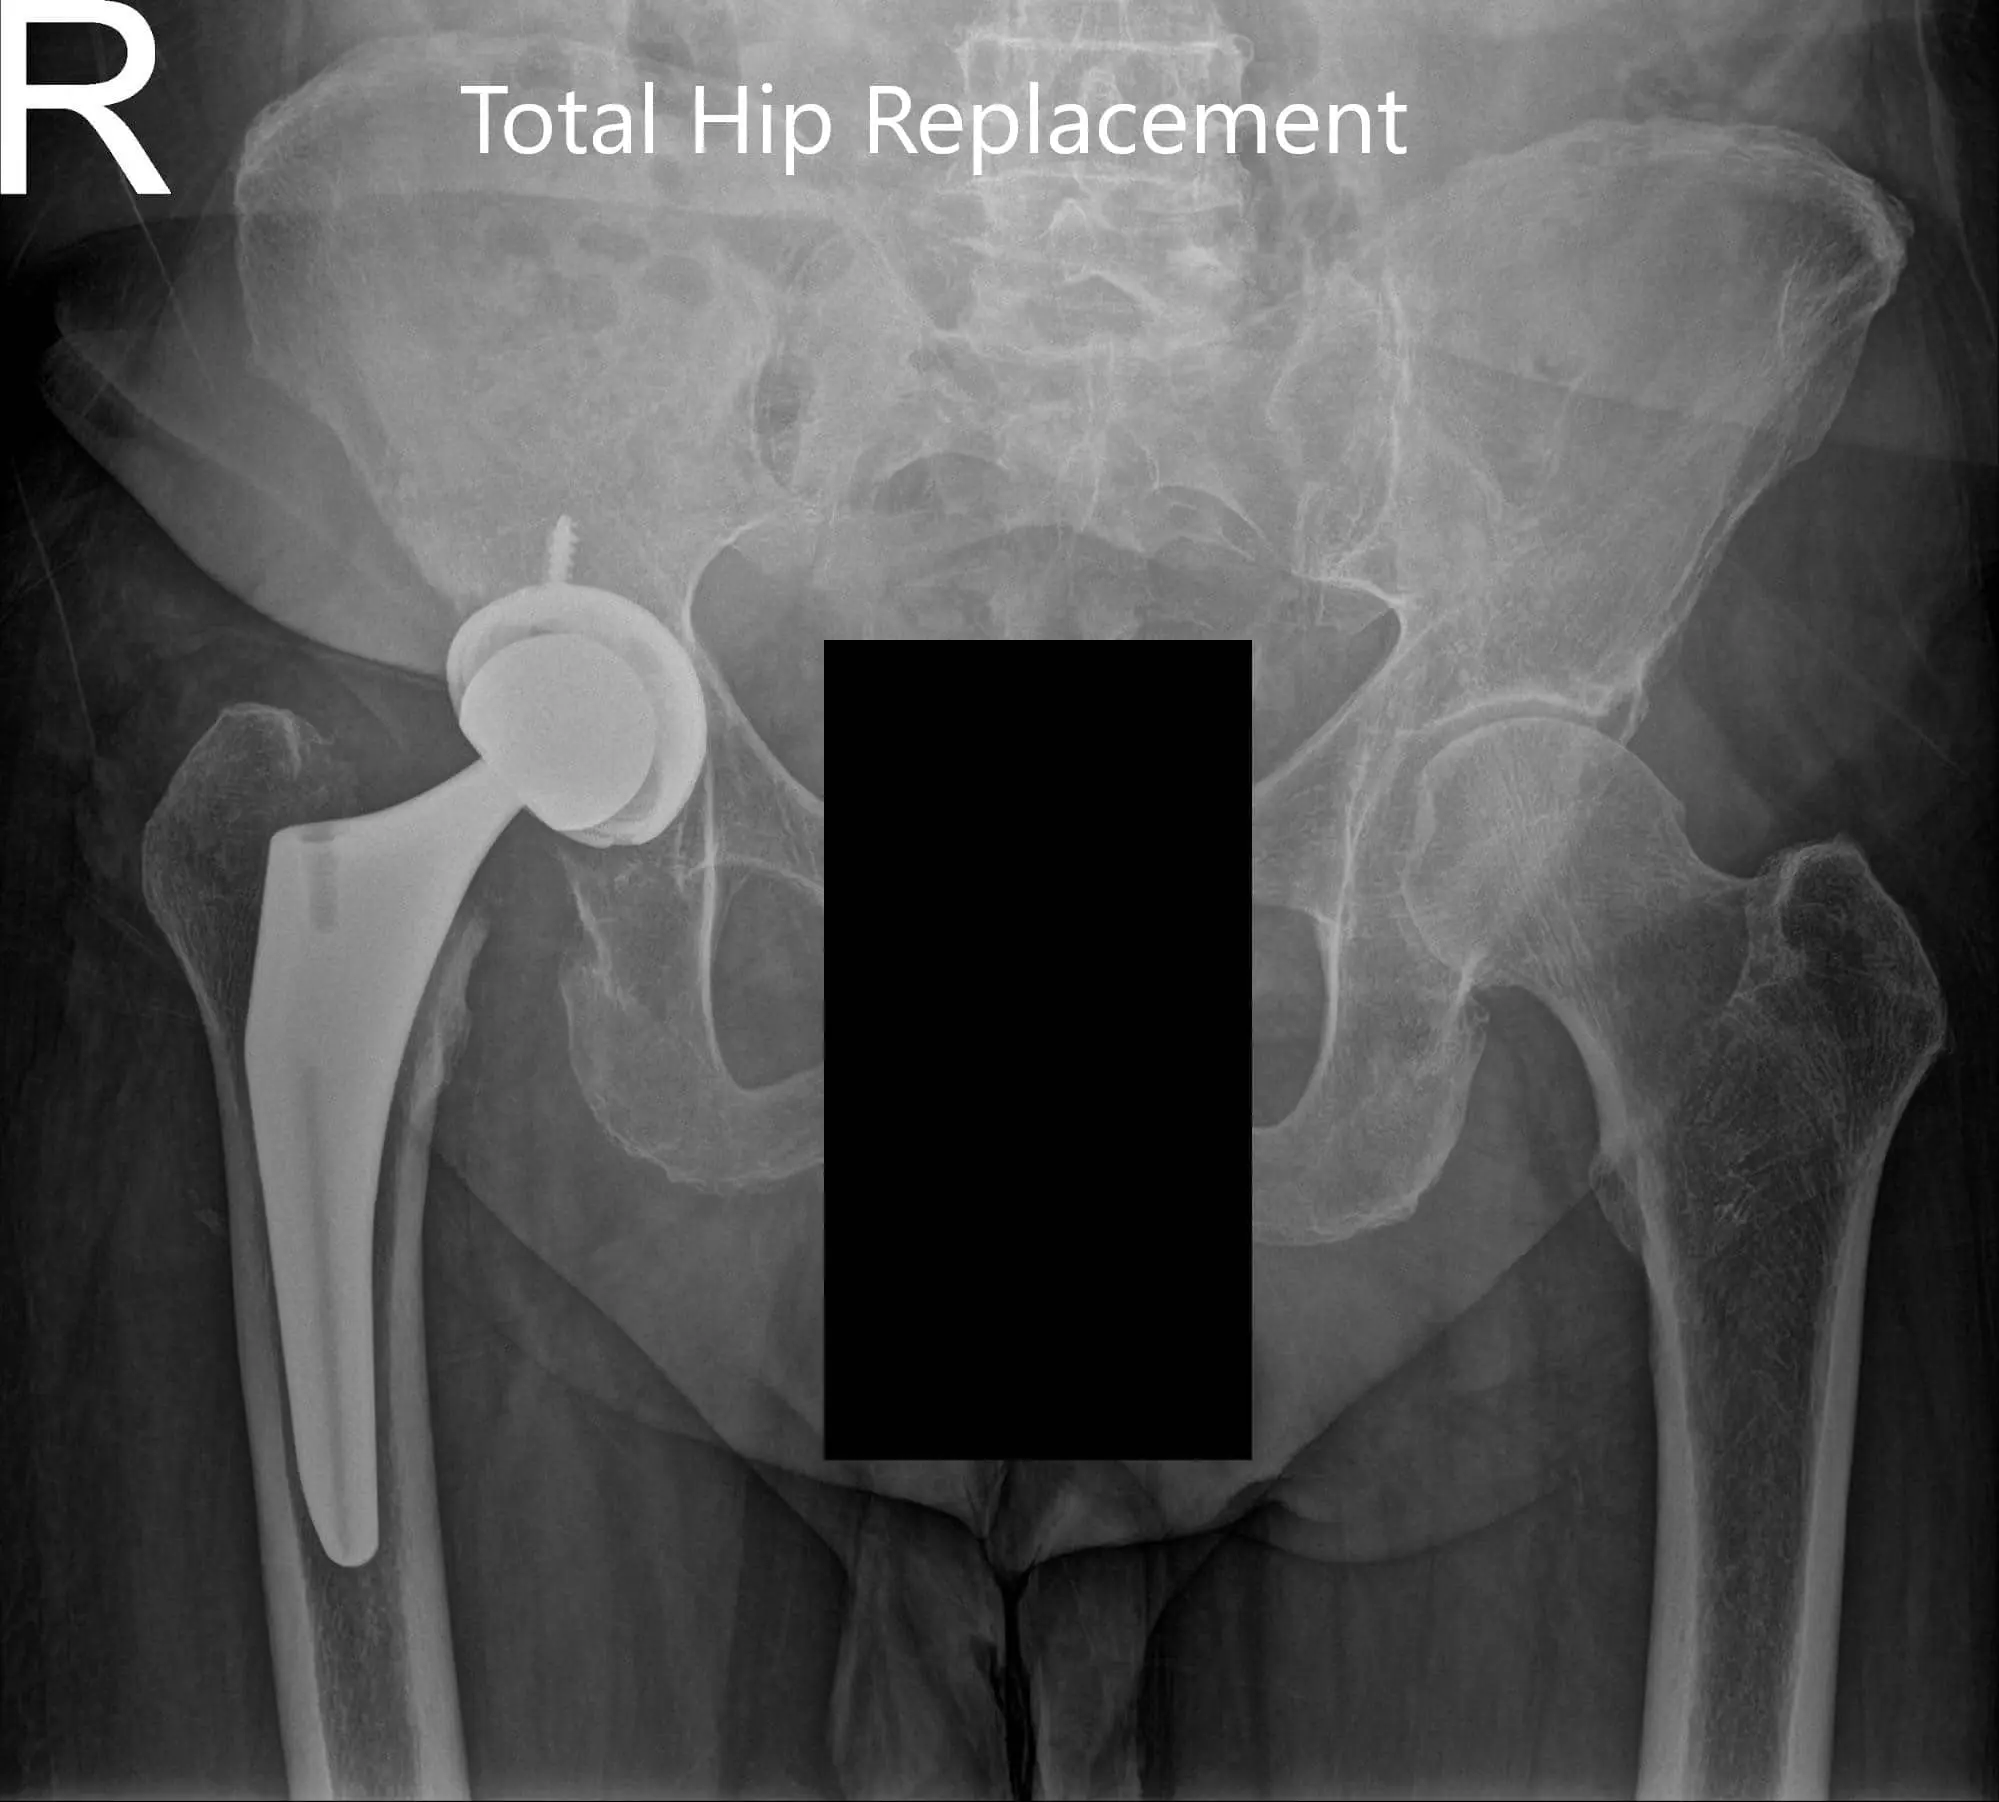

Postoperative X-ray showing the AP view of the pelvis and the frog-legged lateral view of the right hip

Postoperative X-ray showing the AP view of the pelvis and the frog-legged lateral view of the right hip (image-2)